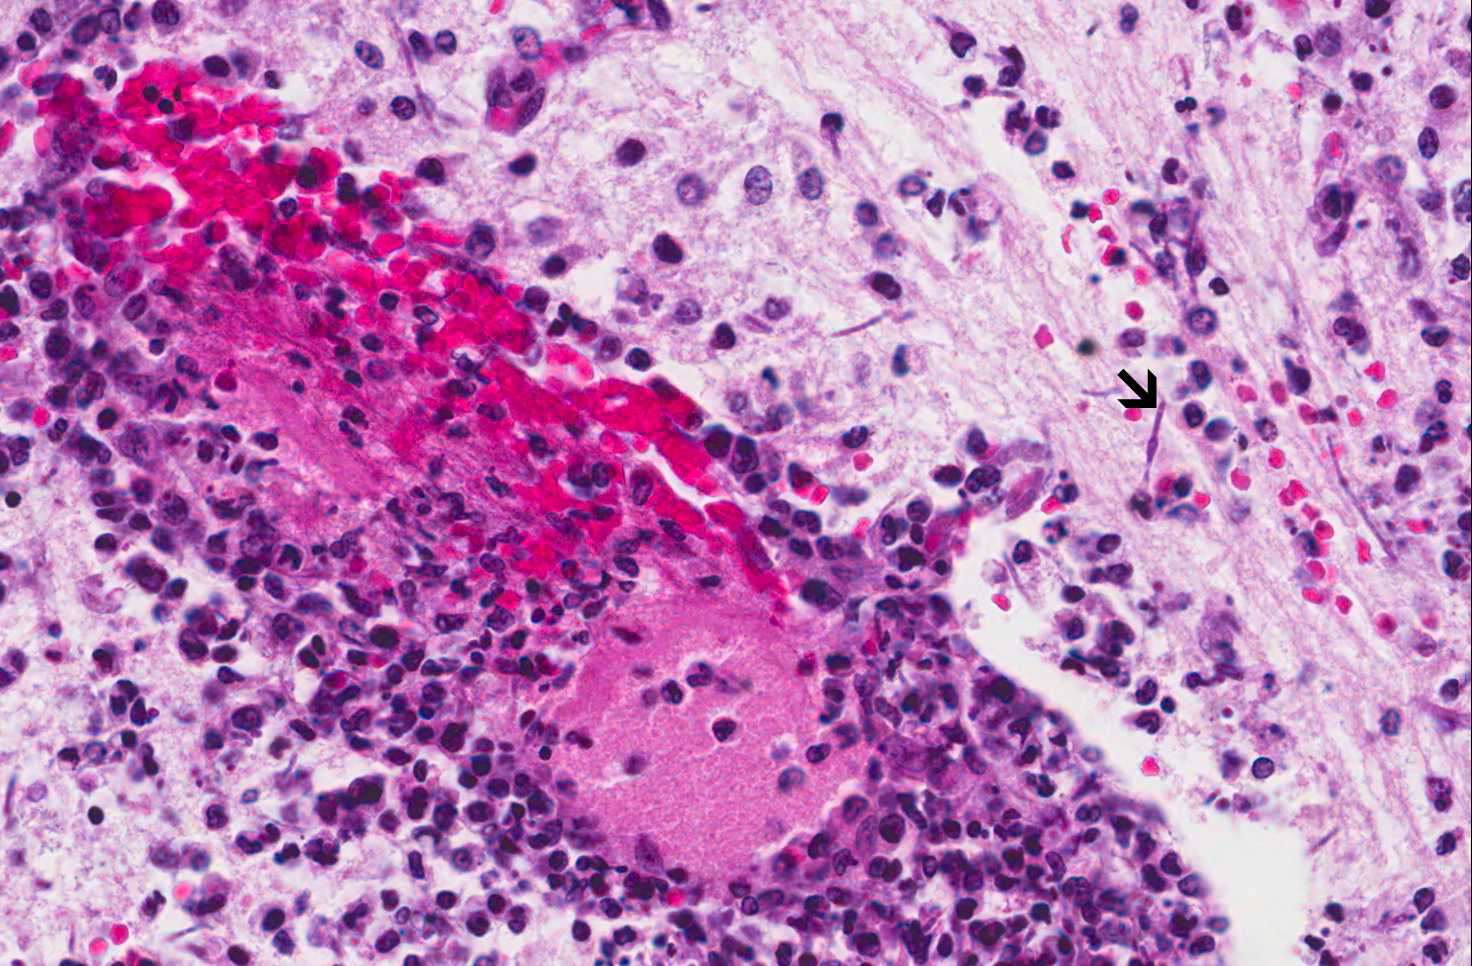

Hematoxylin & eosin

Area 2: In other areas, there is intense perivascular inflammatory cell infiltration. A few fungal hyphae are noted on hematoxylin and eosin stain (arrow).

• In areas with more intense inflammatory cell infiltration (Area 2 and 3), numerous fungal hyphae are present.

• The patient has a history of candida fungal infection and therefore it is not surprise to see candida in the brain. However, a substantial amount of the hyphae are found in areas with little or no inflammatory cell infiltration. This feature, however, suggest post-mortem growth in these areas. The final picture is that of a mixture of pre-mortem and post-mortem growth of candida.